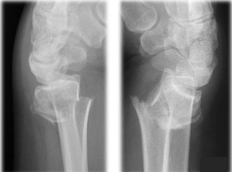

Que fractura se presenta en esta imagen

Colles

Fractura que presenta deformida “En tenedor”